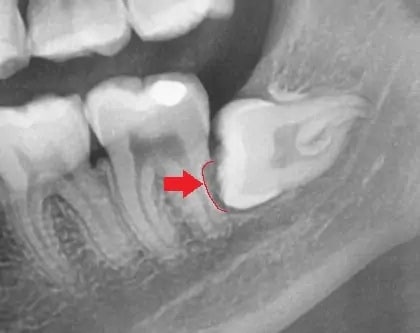

✔ ③ 옆 어금니(제2대구치)를 손상시키는 경우

가장 치명적인 형태예요.

누워난 사랑니가

바로 앞 어금니의 뿌리(root surface)를

서서히 흡수시키거나 충치를 만들 수 있어요.

이 경우는

발치 필요 여부가 거의 “확정” 수준입니다.

위 x-ray 사진의 경우 빨간색 표시된 부분이 앞 치아(어금니)의 뿌리가 사랑니에 의해 흡수된 경우입니다. 이 경우 발치가 필수에요! (출처: https://www.twinkledental.com)